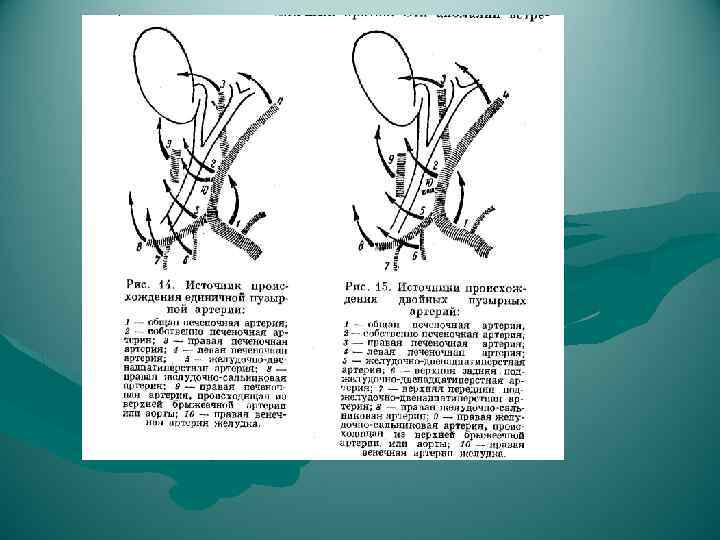

а) Типичное кровоснабжение; б) правая печеночная артерия, исходящая из верхней брыжеечной артерии, в) добавочная левая печеночная артерия, исходящая из левой желудочной артерии; г) сразу же после отхождения от чревного ствола общая печеночная артерия делится на правую и левую ветви, которые проходят друг возле друга, достигая печени через печеночно-двенадцатиперстную связку; д) правая печеночная артерия пересекает общий печеночный проток не сзади, а спереди; е) две пузырных артерии исходят от правой печеночной артерии; ж) пузырная артерия отходит от общей печеночной артерии и пересекает желчный проток не сзади, а спереди; з) пузырная артерия исходит из левой печеночной артерии и пересекает желчный проток спереди; и) имеются две пузырных артерии: одна отходит, как правило, от правой печеночной артерии и достигает желчного пузыря, пересекая общий желчный проток, как и в норме, сзади, тогда как другая пузырная артерия чаще всего отходит от общего ствола печеночной артерии (или от одного из ее стволов) и пересекает общий желчный проток спереди; к) пузырная артерия отходит от левой стороны правой печеночной артерии, при этом оба сосуда образуют петлю; если пузырную артерию перевязать в глубине, то в этом случае в лигатуру может легко попасть и правая печеночная артерия

а) Типичное кровоснабжение; б) правая печеночная артерия, исходящая из верхней брыжеечной артерии, в) добавочная левая печеночная артерия, исходящая из левой желудочной артерии; г) сразу же после отхождения от чревного ствола общая печеночная артерия делится на правую и левую ветви, которые проходят друг возле друга, достигая печени через печеночно-двенадцатиперстную связку; д) правая печеночная артерия пересекает общий печеночный проток не сзади, а спереди; е) две пузырных артерии исходят от правой печеночной артерии; ж) пузырная артерия отходит от общей печеночной артерии и пересекает желчный проток не сзади, а спереди; з) пузырная артерия исходит из левой печеночной артерии и пересекает желчный проток спереди; и) имеются две пузырных артерии: одна отходит, как правило, от правой печеночной артерии и достигает желчного пузыря, пересекая общий желчный проток, как и в норме, сзади, тогда как другая пузырная артерия чаще всего отходит от общего ствола печеночной артерии (или от одного из ее стволов) и пересекает общий желчный проток спереди; к) пузырная артерия отходит от левой стороны правой печеночной артерии, при этом оба сосуда образуют петлю; если пузырную артерию перевязать в глубине, то в этом случае в лигатуру может легко попасть и правая печеночная артерия